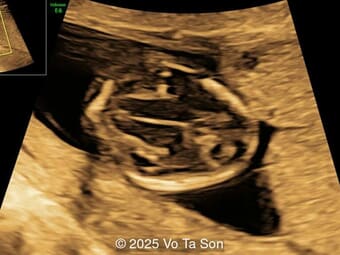

A 35-year-old secundigravida was referred to our unit at 20 weeks gestation for evaluation of suspected fetal skeletal abnormalities. Her first child was healthy, and her personal and family history were otherwise unremarkable. Two years later in a subsequent pregnancy, the patient presented for ultrasound evaluation. This examination was performed at 13 weeks of gestation and demonstrated the following findings: